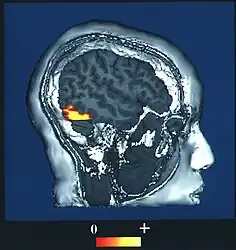

El "área de rostro" FFA está localizada dentro de la red neuronal llamada corriente ventral ubicada en la superficie ventral del lóbulo temporal en la región lateral del giro fusiforme.

El área FFA es lateral y externa al "área de lugar" situada en el parahipocampo. La FFA muestra una cierta lateralización, usualmente siendo más grande en el hemisferio derecho.